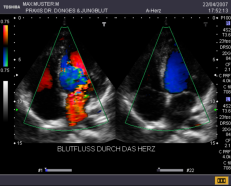

EKG Im Ruhe-EKG sehen wir Herzrhythmusstörungen, abgelaufene Infarkte oder Entzündungen des Herzmuskels. Belastungs-EKG Hier bekommen wir Hinweise auf Ihre körperliche Leistungsfähigkeit und können die Durchblutung der Herzkranzgefäße besser als im Ruhe-EKG beurteilen. Bei verengten Kranzgefäßen zeigt sich oft eine spezielle EKG-Veränderung während der Belastung, ein Herzdruck und/oder Luftnot. Herzultraschall Hier können wir genau die Pumpkraft Ihres Herzens und die Funktion der Herzklappen untersuchen, wir erkennen Infarktnarben, Klappenkrankheiten, Gerinnsel und Gewächse. Der Blutfluss durch die Herzkammern und Klappen kann mit speziellen Verfahren sicht- und hörbar gemacht werden (Farbdoppler). In die Kranzgefäße selbst können wir nicht sehen, aber aus der Beurteilung der Pumpfunktion wichtige Hinweise auf die Durchblutung erhalten. Eine exakte Aussage zu Verengungen der Herzkranzgefäße kann bei entsprechenden Hinweisen aus den Untersuchungen mit einem Herzkatheter getroffen werden. Halsschlagader-Messung Mit unseren hochempfindlichen Geräten können wir den Innendurchmesser der Halsschlagader (Carotis) genau ausmessen. Als Frühzeichen einer beginnenden Aderverkalkung nimmt diese sogenannte Intima-Media Dicke über das Altersmaß hinaus zu. Hieraus ergeben sich wichtige Konsequenzen, so z. B. die Beantwortung der Frage, ob ein erhöhter Cholesterinspiegel schon medikamentös behandelt werden muss.